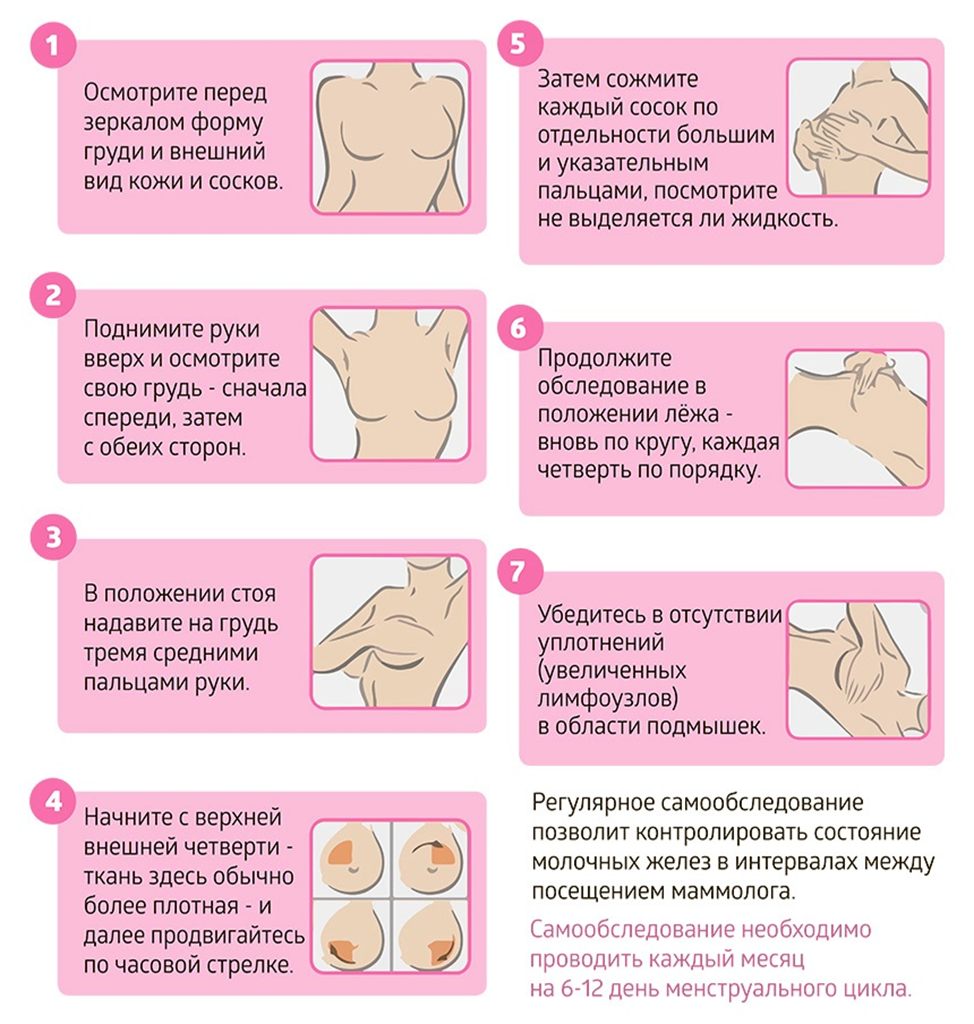

Проводите регулярное самообследование груди для своевременного обнаружения изменений.